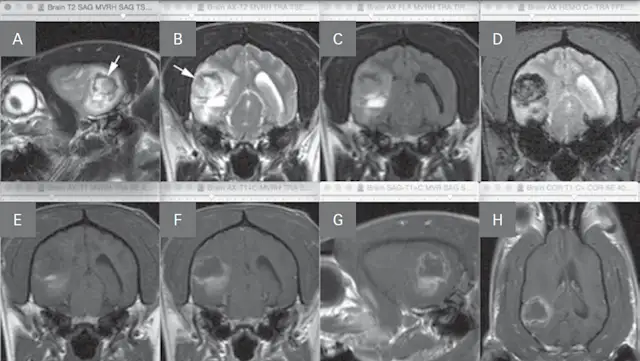

• The classic MRI characteristic of an ischemic stroke (Figure 1, see image gallery below) is an intra-axial lesion (often wedge-shaped) that is hyperintense (bright) on T2-weighted and fluid attenuation inversion recovery (FLAIR) images, iso- to hypointense (dark) on pre-contrast T1-weighted images, and minimal to no contrast enhancement.

FIGURE 1

MRI images of a dog with a right cerebellar infarct (A). Note the wedge-shaped intra-axial lesion in the right dorsal cerebellar gray matter (arrow) that is hyperintense on T2-weighted images (B), isointense on T1-weighted images (C), and does not contrast enhance (D).